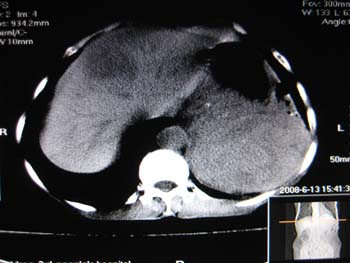

女,65岁,左上腹痛。

肝脏占位  脾脏及胰腺病变   请提供病史

肝脾胃左肾胰都显示不正常啊

病史不详,肝、脾、胰都有占位,谁是原发?

淋巴瘤及肝癌(转移瘤?)可不可以不用一元论解释呢。

胰腺癌伴脾脏侵犯并肝内转移可能性大  建议增强扫描  否则没有确凿的依据

考虑姨尾癌,腹膜后转移\\肝转移

没有病史,没有强化,那就只有猜了,我看病灶很像肝、脾及腹腔多发脓肿,这只是我的意见,

图像欠清,病灶与胃脾胰肾上腺关系显示欠清,建议增强,肝脏考虑转移瘤.

多脏器占位,腹膜后淋巴结增大,淋巴瘤?建议增强扫描